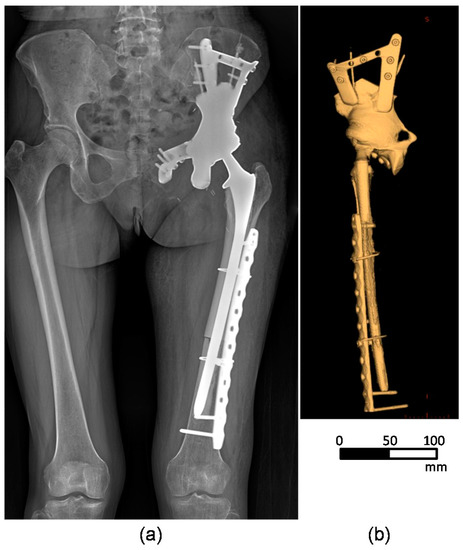

2.1. Patient Information

2.2. 3D-Reconstruction of the Pelvic Implant Model